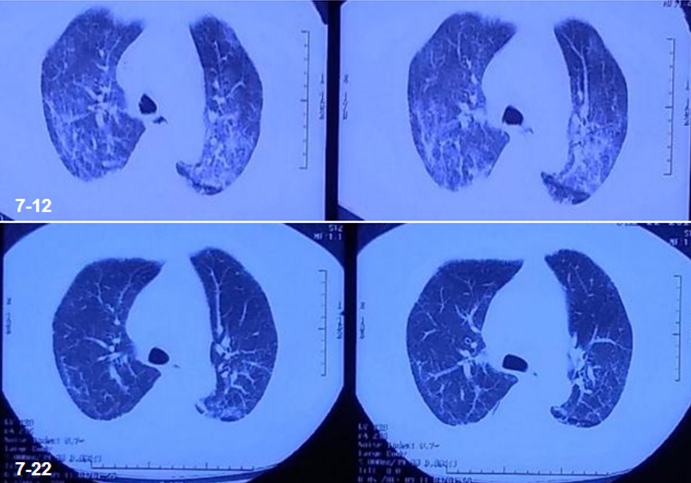

1. 重症鹦鹉热衣原体肺炎病例

患者,男性,60岁;咳嗽、咳痰、发热1周,加重3天,呼吸困难1天,2019年12月9日入院。最高体温39.5℃,伴头痛、肌肉酸痛、咽痛、打喷嚏、流清涕、言语不利。入院当日胸部CT:右肺上叶实变,右肺下叶背段含气囊肿,右侧胸腔积液(图4)。血气分析:FiO2 53%,pH 7.506,PaCO2 28.5 mmHg,PaO2 54.5 mmHg,PaO2/FiO103 mmHg,K+ 3.0 mmol/L,Na+ 124 mmol/L。

入院后患者病情迅速恶化(图5),12月11日行气管插管机械通气。

图5  患者胸部X线片

病原体检测:甲流、乙流病毒IgM,腺病毒、支原体、呼吸道合胞病毒、柯萨奇病毒IgM及血培养均为阴性。痰培养回报洋葱伯克霍尔德菌。12月14日mNGS回报鹦鹉热衣原体(序列数3248)、流产衣原体(序列数166)。

未明确病原体前给予广谱抗感染治疗:莫西沙星+美罗培南+奥司他韦+利巴韦林+利奈唑胺。后经mNGS明确为鹦鹉热衣原体,调整治疗方案。继续使用莫西沙星,加用替加环素,停用利奈唑胺、奥司他韦、利巴韦林,美罗培南降级为头孢哌酮舒巴坦。

给予针对性抗感染治疗后,患者氧合指数逐渐升高,吸氧浓度逐渐下调,WBC基本正常,PCT逐渐下降。患者胸部CT较前明显改善(图6)

图6  患者治疗前后胸部CT比较